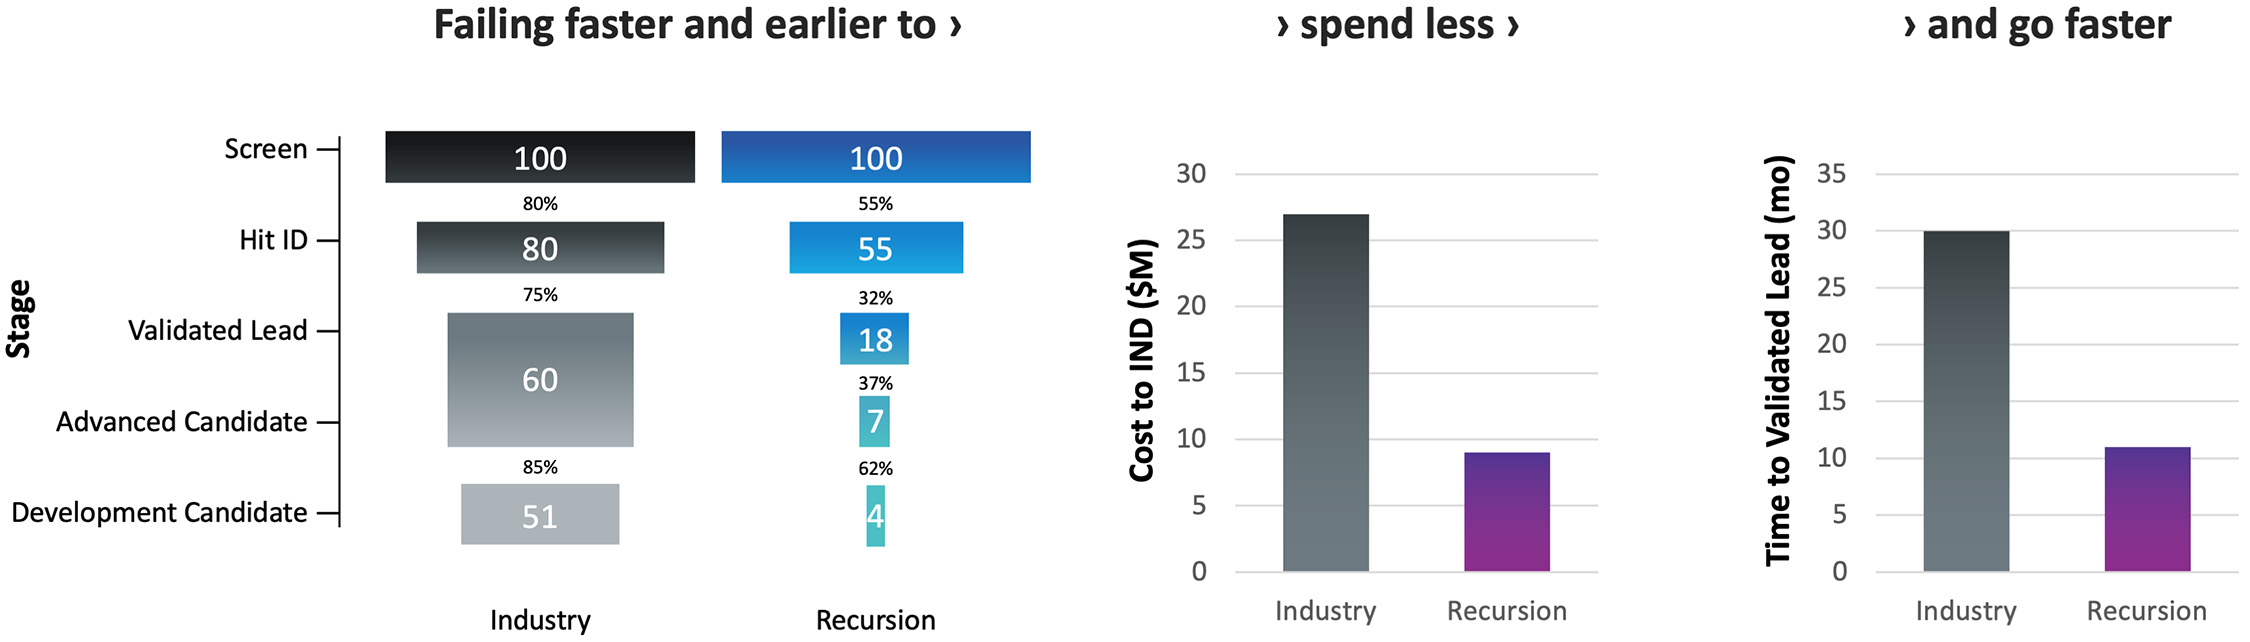

How Recursion is Industrializing the Drug Discovery Process

The traditional drug discovery and development process is characterized by substantial financial risks, with increasing and long-term capital outlays for development programs that often fail to reach patients as marketed products. Historically, it has taken over ten years and an average capitalized R&D cost of approximately $2 billion per approved medicine to move a drug discovery project from early discovery to an approved therapeutic. Such productivity outcomes have culminated in a rapidly declining internal rate of return for the biopharma industry.

Figure 5. Historical biopharma industry R&D metrics. The primary driver of the cost to discover and develop a new medicine is clinical failure. Less than 4% of drug discovery programs that are initiated result in an approved therapeutic, resulting in a risk-adjusted cost of approximately $1.8 to $2.6 billion per new drug launched.3,4,5,6,7

Despite significant investment and brilliant scientists, these metrics point to the need to evolve a more efficient drug discovery process and explore new tools. Traditional drug discovery relies on basic research discoveries from the scientific community to elucidate disease-relevant pathways and targets to interrogate. Coupled with biology’s incredible complexity, this approach has forced the industry to rely on reductionist hypotheses of the critical drivers of complex diseases, which can create a ‘herd mentality’ as multiple parties chase a limited number of therapeutic targets. The situation has been exacerbated by human bias (e.g., confirmation bias and sunk-cost fallacy). Accentuating this problem, the sequential nature of current drug discovery activities and the challenges with aggregation and relatability of data across projects, teams and departments lead to frequent replication of work and long timelines to discharge the scientific risk of such hypotheses. Despite decades of accumulated knowledge, the result is that drug discovery has unintentionally created hurdles for innovation.

At Recursion, we are pioneering the integration of innovations across biology, chemistry, automation, data science and engineering to industrialize drug discovery in a full-stack solution across dozens of key workflows and processes critical in discovering and developing a drug. For example, by combining advances in high content microscopy with arrayed CRISPR genome editing techniques, we can rigorously profile massive, high-dimensional biological and chemical perturbation libraries in multiple human cellular contexts to create digital ‘maps’ of human biology. Leveraging advances in scaled computation, we can conduct massive virtual screens to predict the protein targets for billions of chemical compounds. Similarly, data generated from our automated DMPK module and InVivomics platform enables us to predict ADME properties and identify toxicity signals, respectively, significantly faster than traditional methods. We believe that by harnessing advances in technology to industrialize drug discovery, we can derive novel biological insights not previously described by scientific researchers, reduce the effects of human bias inherent in discovery biology and reduce translational risk at the program outset.